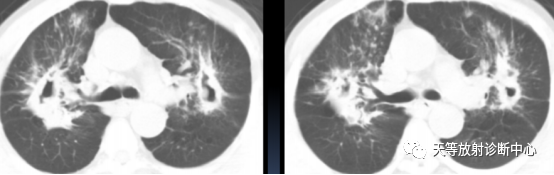

小叶中心结节( 树芽征) 、肺小叶实变、肺段及肺大叶实变、空洞、支气管扩张、病灶内钙化灶、肺不张、肺气肿、肺大疱、肺损毁、纵隔肺门淋巴结肿大( 气管隆突下淋巴结直径≥1.5cm,其他纵隔内淋巴结直径≥1.0cm) 、淋巴结钙化、胸腔积液、胸膜增厚。

▲胞内分枝杆菌肺病,小叶中心结节(树芽征)

▲胞内分枝杆菌肺病,小叶中心结节(树芽征),双肺多发厚壁空洞。

▲胞内分枝杆菌肺病,右肺中叶支气管扩张,右肺下叶小叶中心结节

1、小叶中心结节( 树芽征) :在胞内分枝杆菌组中最常见,其次为鸟分枝杆菌组及脓肿分枝杆菌组,在堪萨斯分枝杆菌组中出现最少。小叶中心结节(树芽征)的形成是由细支气管腔内存在坏死组织及(或)小叶内散在肉芽肿所致,同时反映了支气管及支气管周围炎症。

2、胞内分枝杆菌组中,支气管扩张CT征象的发生率仅次于小叶中心结节。鸟分枝杆菌组及脓肿分枝杆菌组中支气管扩张出现的比例差异无统计学意义。堪萨斯分枝杆菌组出现支气管扩张最少。